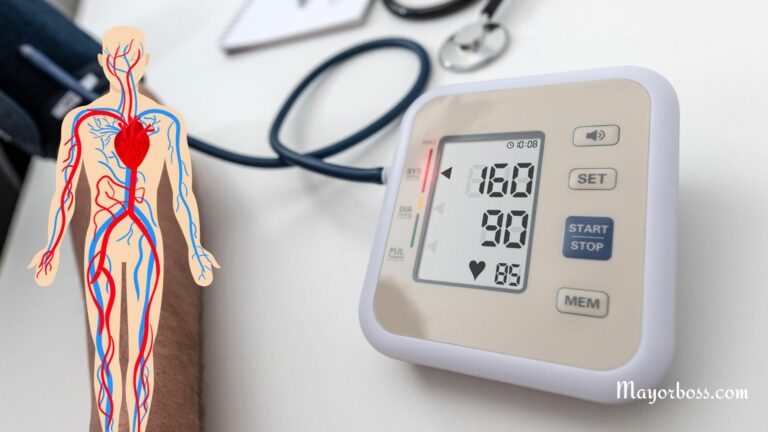

Is 160/90 Blood Pressure High?

Do you want to know if 160/90 blood…